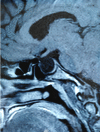

Figure 1

sagittal spin echo T1-weighted image showing the macro-adenoma